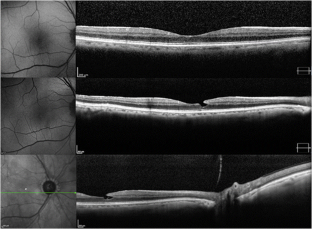

Thirty-five patients were included. At baseline, six fellow eyes (17%) showed a normal foveal profile, 26 (74%) had a tractional ERM, and three cases (9%) revealed a bilateral LMH, one of them with a lamellar hole-associated epiretinal proliferation (LHEP). A posterior vitreous detachment (PVD) was present in 29 patients (83%), four (11%) had only a vitreo-papillary adhesion (VPA), and two (6%) had both vitreo-macular adhesion (VMA) and VPA. After a mean follow-up of 4.6 ± 1.9 years, one eye (3%) developed a vitreous detachment from the macula with persistent VPA, and one developed a PVD from a VPA with subsequent ERM formation.

BCVA and mean CFT remained stable in 35 eyes (100%). Likewise, no B-FAF signal variations were detected. One patient developed a LMH during the 3rd year of follow-up.

Our data suggest that the presence of a LMH in one eye does not increase significantly the risk of developing the same condition in the fellow eye after 4 years. Bilateral condition is uncommon, and an ERM is often detected in the fellow eye. LHEPs were not observed in fellow eyes with foveal integrity, and all LHEPs observed (in main and fellow eyes) were always associated with LMHs; this supports the hypothesis that LHEP is a consequence and not a causative factor for LMHs. The occurrence of a LMH in one fellow eye after 3 years follow-up may suggest that a higher incidence of bilateral disease could develop in a longer time span.

Fig. 3